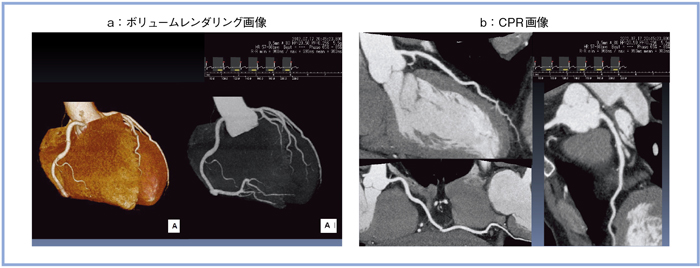

正常冠動脈を心電図同期フラッシュスキャンにより5心拍5秒で撮影した(図3)。ボリュームレンダリング画像(a)はもちろん,CPR画像でも(b),末梢の細い血管まで明瞭な画像が得られた。

図3 心電図同期フラッシュスキャンによる正常冠動脈CT画像